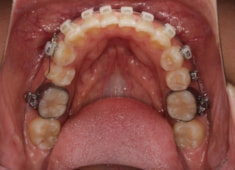

治療開始から5ヶ月後